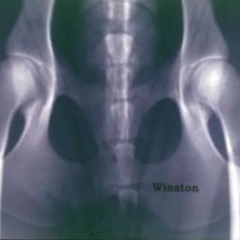

- Hip radiographs were taken by a veterinarian with the dog in the hip-extended, supine position according to the American Veterinary Medical Association guidelines and were sent to the OFA by the owner. The radiographs were independently evaluated by 3 randomly selected board-certified radiologists from a pool of 20-25 (concordance rates average 74% over 1.8 million radiographs).

- For hip dysplasia, dogs were scored into seven categories: excellent, good, fair, borderline, mild, moderate and severe hip dysplasia. The first three categories (excellent, good and fair) are generally considered “normal” dogs although they will carry some of the mutations that contribute to hip dysplasia. The last three categories (mild, moderate and severe) are considered “dysplastic” dogs.

- Further details on the breeds and the scoring criterion can be found in this published paper. A new manuscript is in preparation. Images of dogs with good and poor (dysplastic) hip conformation and also a tomographic slice through the elbow of a dog with fragmented medial coronoid process (part of the elbow dysplasia syndrome) can be seen below.